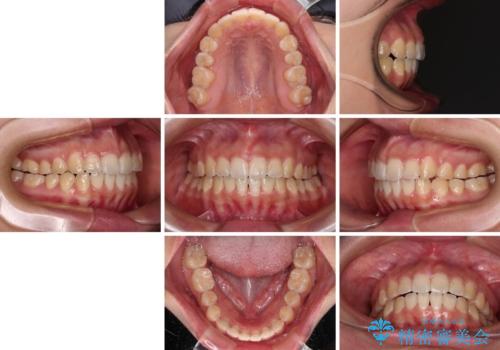

インビザライン単体で改善することも可能ですが、達成する可能性が高くないため、カリエールディスタライザーという補助装置を併用して、より確実性を上げることとしました。

奥歯の咬み合わせを改善しながら、並行してインビザラインで歯列を整えることとしました。

カリエールディスタライザーを併用したことで、確実かつ短期間で治療を終えることができました。